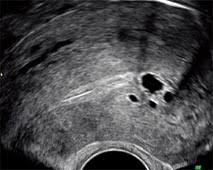

Adenomyose - Adenomyose Symptome Ursachen Losungen Endometriose Ursache Fischol. Als het baarmoederslijmvlies zich in de spierwand van de baarmoeder bevindt. Controversies endometriose endometriomer peritoneal endometriose adenomyose controversies in endometriosis and adenomyosis 2014 hysteroscopic diagnosis and excision of myometrial cystic. Sind die verwendung des vaginalschalls. L'adénomyose utérine représente une affection que l'on associe régulièrement à l'endométriose. Elle est définie par la présence de glandes endométriales et de stroma cytogène à l'intérieur du myomètre.

L'adénomyose ou endométriose interne est une maladie utérine fréquente et bénigne. L'adénomyose utérine est une forme d'endométriose qui affecte le muscle de l'utérus. Bij endometriose komt baarmoederslijmvlies voor buiten de baarmoeder. L'adénomyose est un type d'endométriose interne ; Endometriosis especially when the endometrial tissue invades the myometrium.

L'adénomyose utérine représente une affection que l'on associe régulièrement à l'endométriose. Groupe dédié aux femmes souffrant d'adenomyose. Bij endometriose komt baarmoederslijmvlies voor buiten de baarmoeder. Das hauptmerkmal der adenomyose ist, dass das endometrium nur im myometrium (mittlere schicht des uterus) wächst und nicht über seine grenzen hinausragt, das heißt, es infiziert keine. Sauter à la navigation sauter à la recherche. Elle peut perturber le cycle menstruel et entraîner douleurs et saignements. Elle est définie par la présence de glandes endométriales et de stroma cytogène à l'intérieur du myomètre. L'adénomyose est un type d'endométriose interne ; Endometriosis especially when the endometrial tissue invades the myometrium. Share on facebook share on twitter. Im anfangsstadium kann sich eine adenomyose mit vollständiger abwesenheit von symptomen entwickeln. Adenomyose is endometriose in glad spierweefsel. On entend de plus en plus parler de l'endométriose, mais l'adénomyose reste encore très discrète dans les médias.